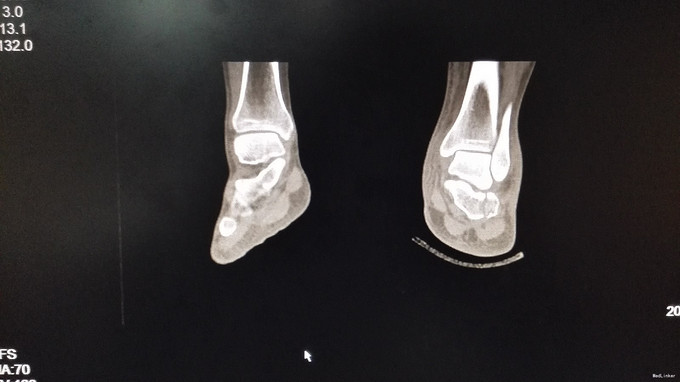

左足跟淤血肿胀明显,无明显畸形,皮肤完整,局部压痛明显,可扪及骨擦感,纵向叩击痛阳性,足趾活动正常,末梢血运、感觉正常。左跟骨X片示:左跟骨粉碎性骨折,左足部CT示:左侧跟骨粉碎性骨折,累及跟距关节面。

左跟骨粉碎性骨折,排除手术禁忌症后行左跟骨粉碎性骨折切开复位内固定术。

中年男性患者,因“跌倒致左足跟部疼痛、活动受限4小时”入院,左跟骨X片及左足部CT提示:左跟骨粉碎性骨折,累及跟距关节面。结合临床症状、体征及影像学检查,诊断左跟骨粉碎性骨折,且累及关节面,手术指征明确,排除手术禁忌后行切开复位内固定术,术后复查X片示对位良好。出院1月后复查,1月内避免负重。